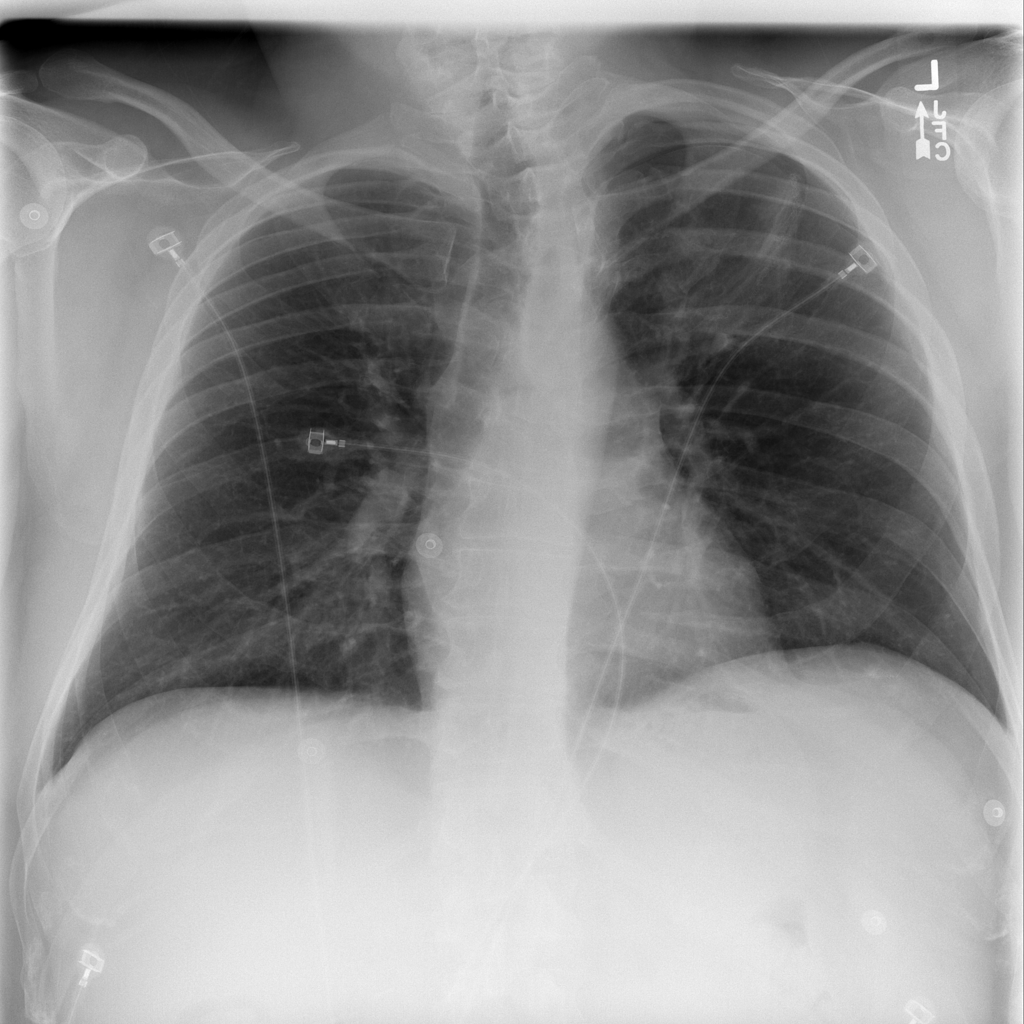

PAT-4639 · IMG-011Pneumothorax

PAT-4639 · IMG-011

AP